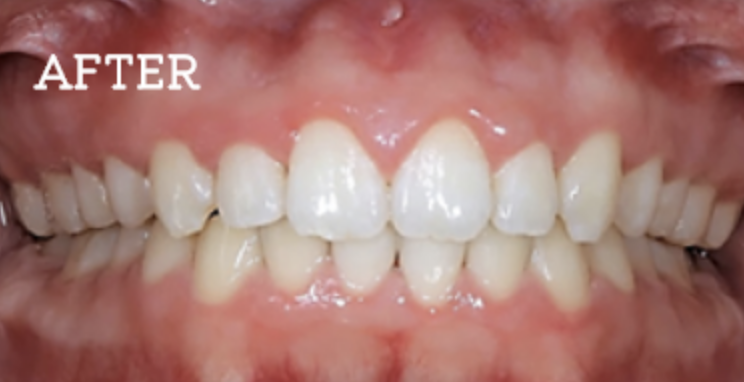

20年以上も持続する治療効果の実現

当院では一時しのぎではなく根本的な治療を行うことで、治療効果の持続性を実感できます。

定期的なメンテナンス調整は必要ですが、実際の症例として、治療後20年以上も改善された口腔を維持されている患者様もおります。

お困りごとを参考に、治療のbefore・afterが確認できます。治療過程や期間、費用などを参考にご覧ください。